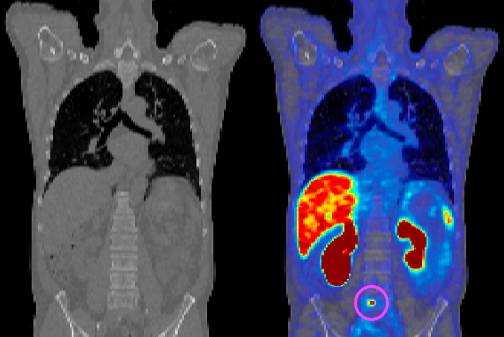

The images were also graded on image quality on a 5-point Likert scale in three categories: an overall image quality score indicating if the image was acceptable for diagnostic purposes, a score for the ability to identify lesions, and a score for the perception of noise within the image.

T-test results showed no statistically significant differences in the Likert scores for image quality for different uptake times (60-70 minutes and 90-100 minutes), with all of the studies being of good diagnostic quality, the authors wrote. Liver signal-to-noise ratio (SNR) calculated at both 60-70 minutes and 90-100 minutes showed no statistically significant difference, either. While there was a greater range of liver SNR for images scored between 3 and 3.5, there were no statistically significant differences between the 60-70 minute and 90-100 minute uptake time groups using either the Likert scores or liver SNR as metrics.